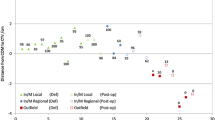

After segmentation of the local recurrence the dose evaluation was performed on follow-up CT scans. The initial dose distribution derived from the original treatment plan was correlated with the recurrence volume on the follow-up images. We calculated the DVH statistics of the 8 patients with 3D conformal radiation therapy for the base and boost plan separately (see Table 1). These plans were applied sequentially. We excluded the IMRT patient as the boost dose is calculated into one sum plan for radiation and we had no separate dose files available for evaluation. Figure 1 shows the percentage of the recurrence volume within the 80%-isodose volume.

The measurement of the location of the recurrence within the boost volume, boost + 1 cm, boost + 1.5 cm and boost + 2 cm volumes is described schematically in Figure 2. Patient 9 had a biliary stent in the follow-up CT but not initially. This made segmentation difficult for the physician because of subsequent transposition of anatomic structures in comparison to the initial CT scan. Weight loss was clearly seen in all patients in the follow-up CTs. Particularly the mesenteric and subcutaneous fat tissue decreased, which cannot be taken into account very well by both the automatic algorithms and the physician during registration.

Patient 7, 8 and 9 had large recurrences growing within the boost volume/border and outfield up to 6.26 cm, 4.05 cm and 1.99 cm respectively (measured on one representative axial slide). This can also be seen in the calculated results in in Figure 1. Only 20%, 0% and 12% of the recurrence volume of patient 7, 8 and 9, respectively, lie within the 80%-isodose volume.

Patient 3 had a severe deformation in the follow-up CT scan (see Figure 3) compared to the planning CT. That might be the reason for the different finding of the physician and automatic calculation. In the validation process, the physician found the recurrence to be within the boost and boost + 1 cm volume. However, the automatic algorithm calculated 84% in the PTV and only 15% in the boost 80%-isodose volume.

The validation showed a very well match for patient 1 and 2 as well as 5 and 6 (cp. Table 2). For patient 1 and 2 the recurrence laid in the PTV 90% and 100%, respectively. For patient 2 the algorithm calculated 98% match for the boost volume; patient 1 had no boost VOI delineated for calculation. Recurrences for patient 5 and 6 were in the boost volume and slightly outside (1 cm and 1.15 cm), which correlates with the validation results to be within the boost + 1 cm volume for patient 5 (algorithm 88% match); and within the boost + 1.5 cm volume for patient 6 (algorithm 95% match).

Recurrence analysis demonstrated that all recurrences except one occurred within the defined GTV/boost volume; one recurrence developed beyond the field border/outfield. With the defined distance volumes in relation to the recurrences, we could show that most recurrent lesions were within the 2 cm radius of the primary tumor (cp. Figure 2). Two large recurrences extended beyond the 2 cm, however, this might be due to very rapid growth and/or late detection of the tumor progression. Analysis of the spatial relationship of the recurrences proved the concept that extension of the CTV/PTV into the ventro-lateral regions of lymphatic spread of approximately 2 cm encloses the regions of tumor recurrence. No growth dorsally in the region of the boost was observed; therefore, no significant enlargement into this region seems required. Additionally, no difference between the lateral right-left sides could be shown.